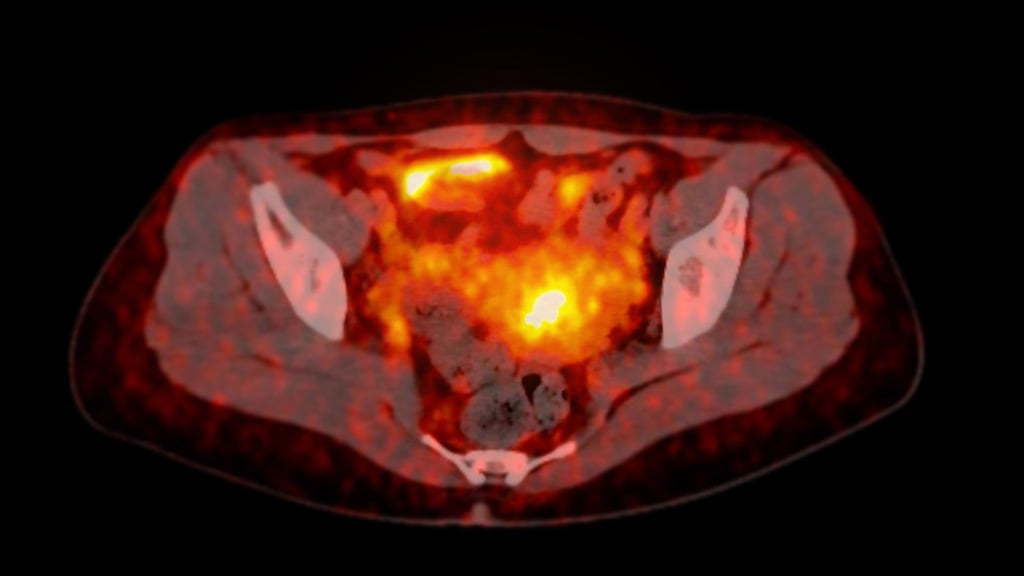

From our legacy in nuclear imaging to our future vision of theranostics, we never leave the picture.

From diagnosis to treatment, our sole focus is delivering effective, targeted, and seamless solutions that enhance the lives of patients living with cancer.

With more than 100+ years' experience, Curium is leveraging its expertise to help transform the treatment landscape with a robust precision theranostics pipeline.